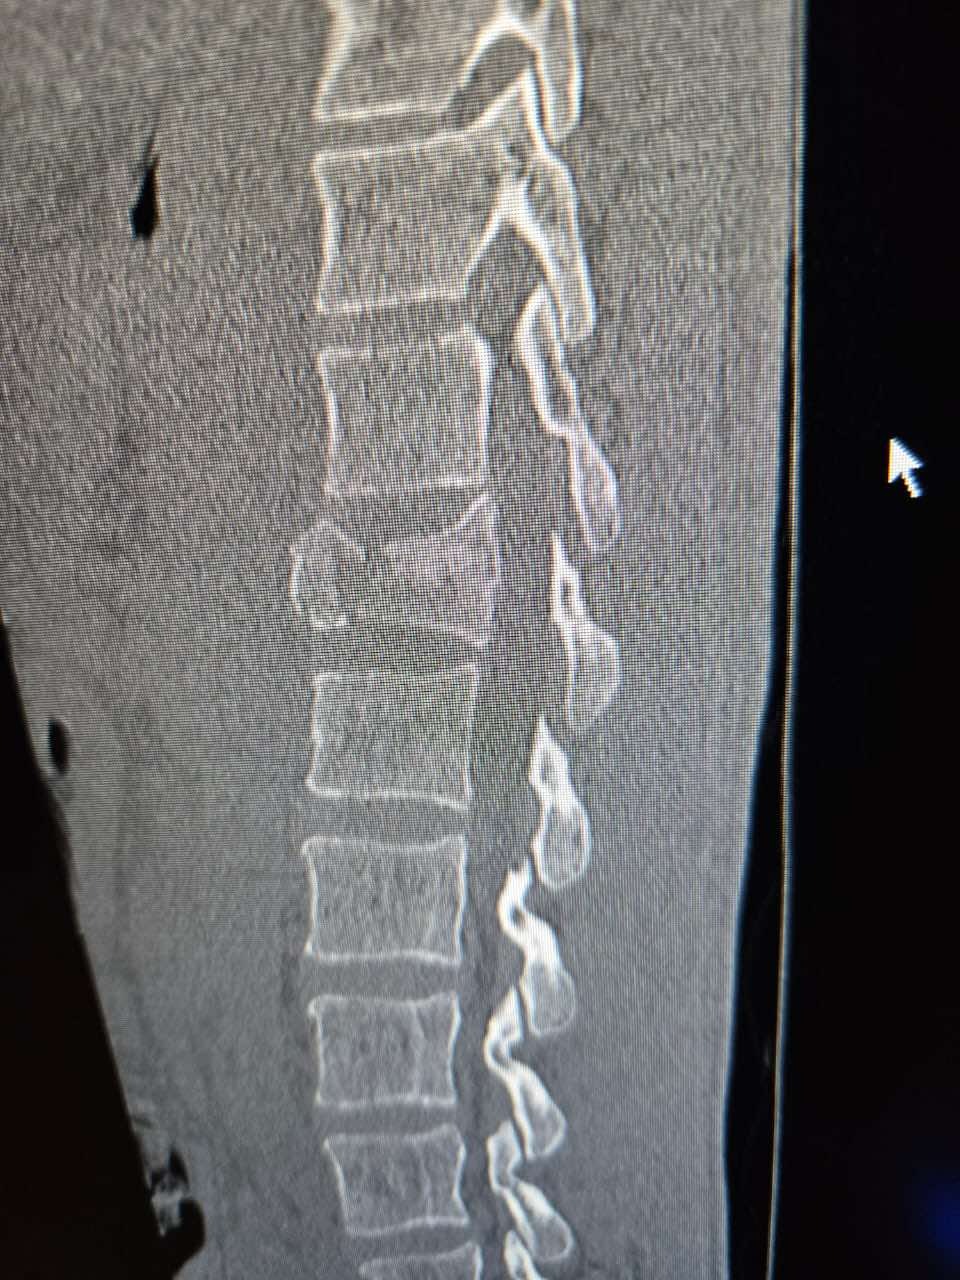

A few days ago, while surfing near Puerto Escondido, Mexico, our dear friend Vincent “Vinnie” Cook had a terrible accident. He free-fell from a large wave and landed hard on his tailbone. The impact caused a compression fracture of his T12 vertebra, a serious spinal injury that requires surgery to stabilize his spine and prevent long-term damage.

We’re beyond grateful that Vinnie is not paralyzed — but his recovery journey will be long and costly. Doctors have advised that he will need surgery as soon as possible, followed by three to six months of recovery, during which he won’t be able to work.